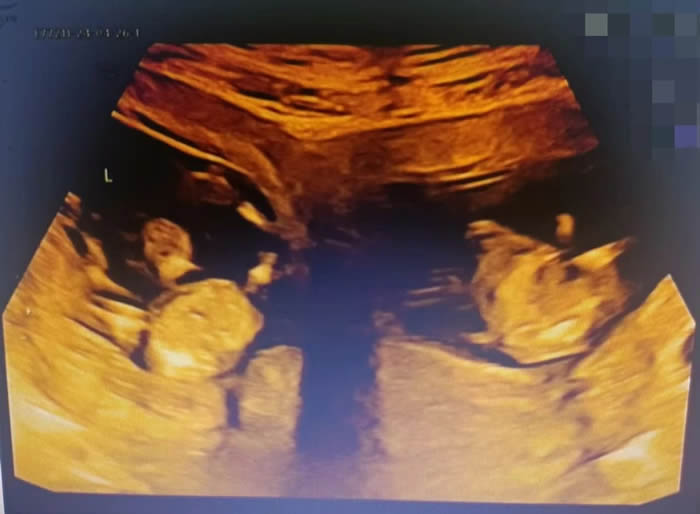

各科醫(yī)護(hù)配合默契,主刀醫(yī)生沙小龍手法嫻熟,開腹、取子一氣呵成。手術(shù)開始僅4分鐘,伴隨著一聲清脆的啼哭,第一個(gè)孩子成功取出,女孩,1.6千克,2分鐘后,男孩出生,體重2.03千克。

早早等在一旁的新生兒科醫(yī)生立刻為兩個(gè)孩子進(jìn)行檢查,隨后轉(zhuǎn)入新生兒病房進(jìn)行救治。為了預(yù)防產(chǎn)后出血,取出龍鳳胎后,沙小龍醫(yī)生第一時(shí)間用藥促進(jìn)子宮及時(shí)收縮,兩個(gè)子宮緊緊貼在一起,形成了一個(gè)完整的心型。